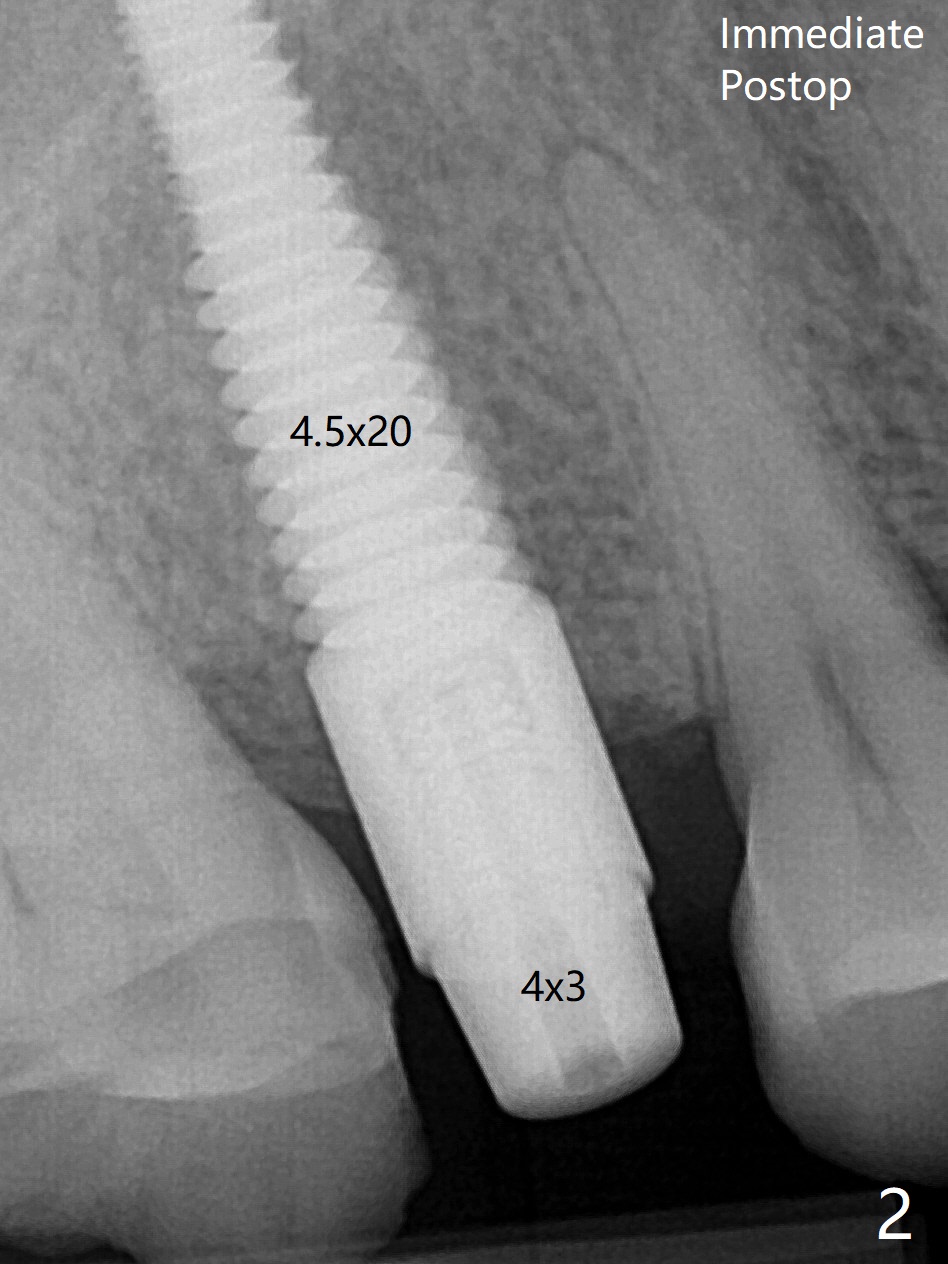

The nervous patient is not pleased with lengthy free hand procedure and pressure from sinus lift in spite of seemingly sufficient anesthesia (Fig.2).  Later the implant is placed deeper ~ .5 mm for restoration because of the short vertical dimension.  The threads remain subcrestal, while bone graft keeps supracrestal (Fig.5 *).  In spite of severe occlusal wear, the patient refuses night guard.